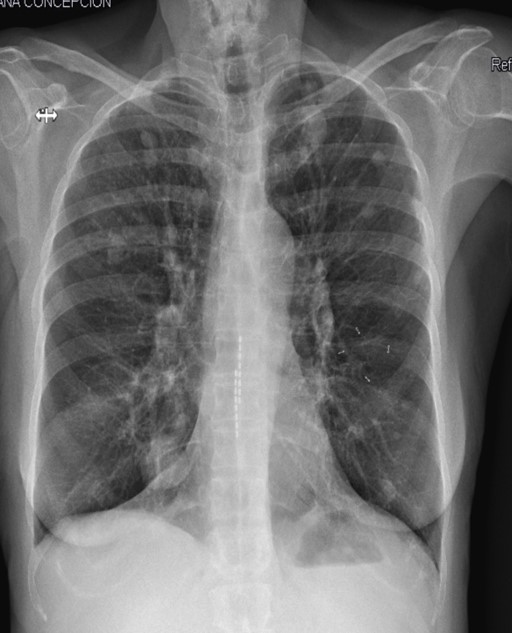

Tras la evaluación clínica y las pruebas realizadas, la paciente fue remitida a urgencias para ingreso hospitalario y estudio. Allí se realizó una biopsia que confirmó el diagnóstico de carcinoma suprarrenal maligno en estadio IV. Se inició tratamiento con quimioterapia.

Después de las pruebas realizadas desde Atención Primaria, en ingreso llevaron a cabo TAC toracoabdominal y biopsia que confirmó el diagnóstico. Se comentó con Oncología médica quedando la paciente a su cargo y se inició quimioterapia.

Este tipo de tumores afecta con más a mujeres adultas en edad media, aunque puede presentarse en pacientes mayores. Sus síntomas suelen ser inespecíficos, lo que complica su detección temprana. El tratamiento depende de la etapa de la enfermedad; en fases iniciales se prefiere cirugía, en estadios avanzados quimiorradioterapia. En general, el pronóstico es desfavorable. Las glándulas suprarrenales son sitio frecuente de patología que hay que conocer y manejar desde Atención Primaria porque el envejecimiento poblacional y la creciente demanda de pruebas radiológicas conllevan a un aumento en la detección de lesiones suprarrenales indeterminadas.